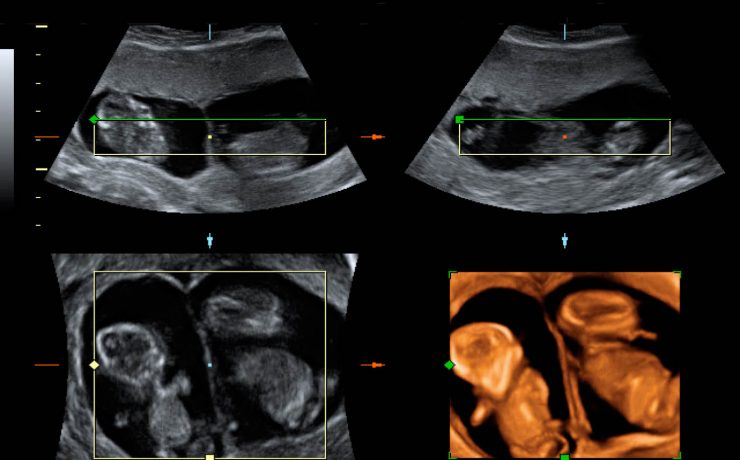

Protocolo de exploración de la vesícula biliar

El estudio ultrasonográfico de la vía biliar requiere que el paciente este en ayunas de 6 horas, puesto que la ingesta de alimentos, sobre todo de naturaleza grasa, provoca la contracción o el colapso de la vesícula biliar, también reduce el gas intestinal que dificulta la evaluación ecográfica de la